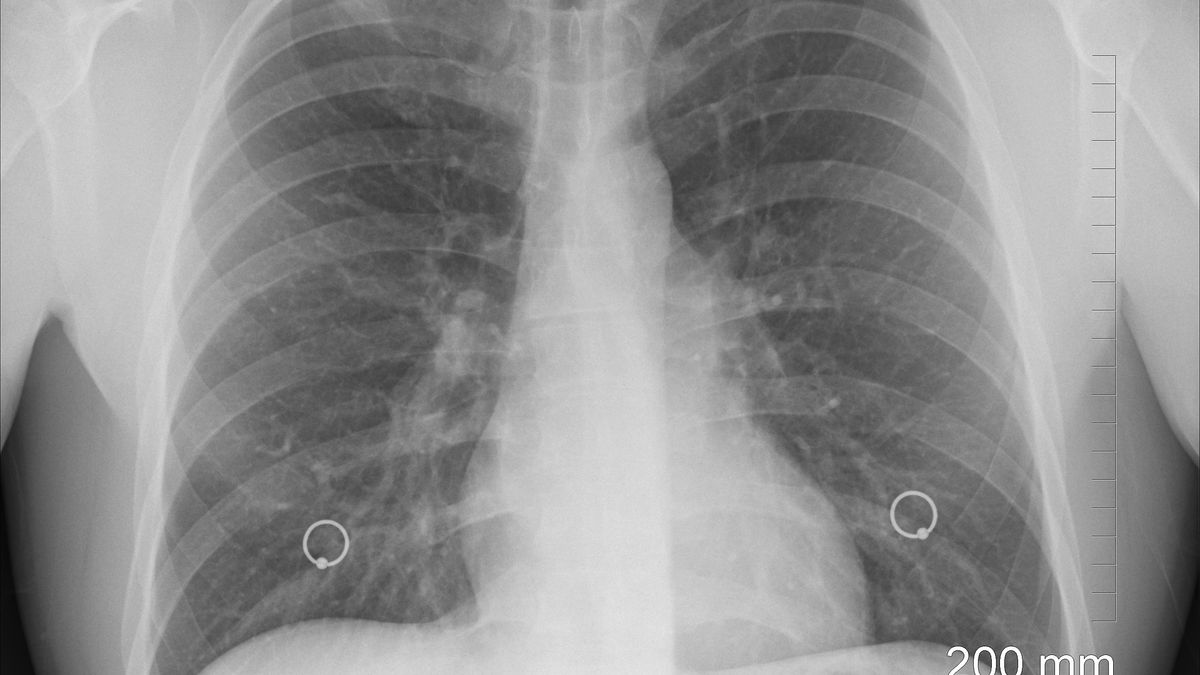

Doskonale oczyszczają płuca. Niesamowicie poprawiają też wydolność oddechową

Nie od dzisiaj wiadomo, że wieloletnie palenie papierosów negatywnie odbija się na kondycji naszych płuc. Jednak dzięki odpowiedniej diecie można poprawić wydolność oddechową. Oto lista produktów, dzięki którym oczyścisz swoje płuca.